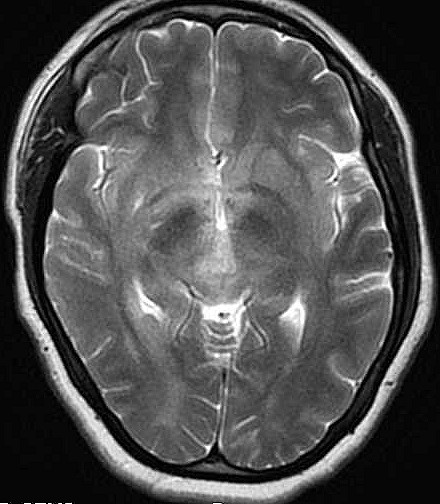

| Fem. 17a. |

| Nódulo sólido homogêneo preenchendo o III ventrículo, com limites precisos, com hipossinal em T1 e hipersinal em T2 e FLAIR, que se impregna por contraste paramagnético. Lesão menor implantada no assoalho do IV ventrículo provavelmente representa disseminação por via liquórica. |

| F. 17a. Tumor teratóide rabdóide atípico de III ventrículo. RM | HE | VIM, GFAP | HHF35, desmina, 1A4 | AE1AE3, EMA |